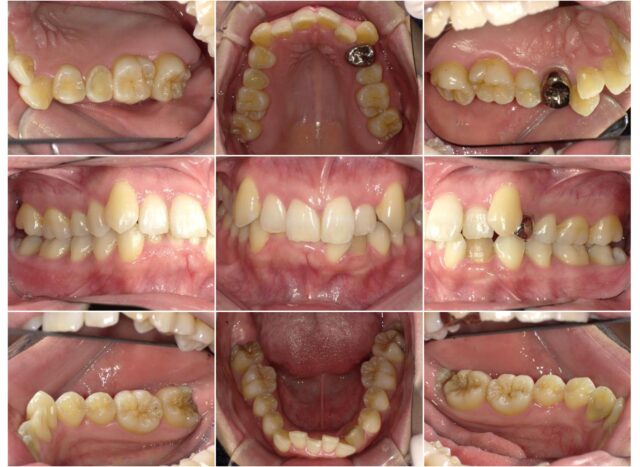

症例紹介

before

after